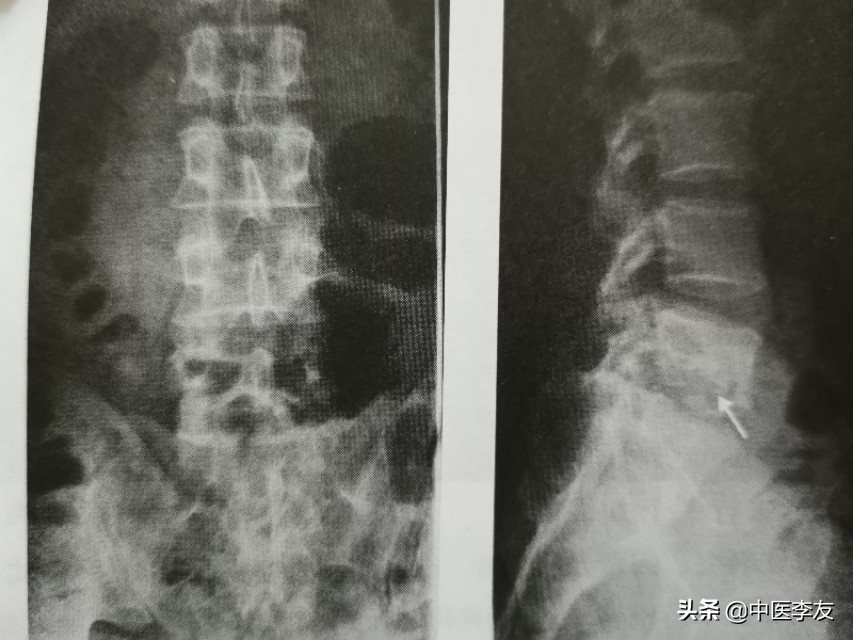

1.X线:①骨质破坏:表现为低密度骨质缺损区,边缘无硬化。

②椎间隙变窄或消失,因椎间盘及软骨终板被破坏,椎间盘破坏严重者可导致相邻的椎体融合在一起,为诊断脊椎结核的重要依据。

③后突畸形:为脊椎结核较特征性表现之一,为多个椎体明显破坏所致。

④冷性脓肿:腰椎结核可形成腰大肌脓肿,表现为腰大肌呈弧形向外突出高密度影,胸椎结核形成椎旁脓肿,表现为胸椎两旁梭形软组织肿胀高密度影,颈椎结核形成咽后壁脓肿,表现为咽后壁软组织影增宽,并呈弧形前突,较长时间的冷性脓肿可有不规则钙化。

依据骨质最先破坏的部位可分为:①中心型,又叫椎体型,表现为椎体内圆形或不规则形的骨缺损区,边缘不清,内可有小泥砂状死骨,后期椎体常塌陷变扁或呈楔形,甚至整个椎体消失,此时骨质破坏和死骨不好观察。

②边缘型(椎间型),破坏开始于椎体的上、下缘,向椎体内和椎间盘侵蚀蔓延。